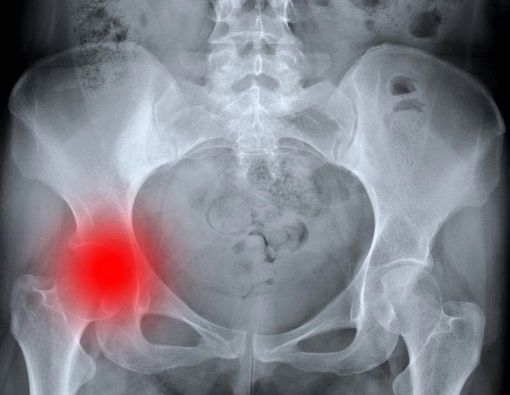

Patah tulang bisa terjadi di bagian mana saja pada tubuh. Panggul menjadi satu bagian tubuh yang sering mengalami patah tulang. Yang di maksud patah tulang panggul adalah patah tulang pada seperempat atas bagian tulang femur (paha). Luas dari patah tulang tersebut bergantung pada gaya/kekuatan dari trauma yang terlibat.

Patah tulang panggul biasanya disebabkan akibat jatuh atau hentakan langsung pada bagian panggul. Beberapa kondisi medis yang dapat menyebabkan patah tulang panggul, seperti:

Ketiga hal tersebut dapat merapuhkan tulang dan membuat panggul lebih berisiko untuk mengalami patah tulang. Pada kasus tertentu, patah tulang panggul masih mungkin terjadi walau seseorang hanya berdiri dan memutar badannya.